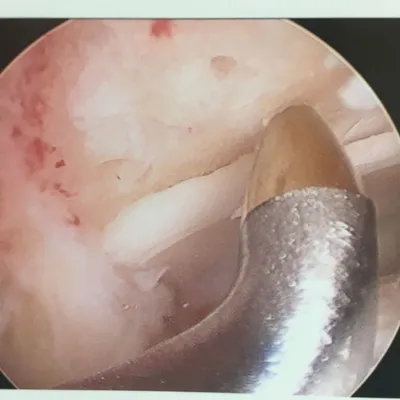

Series of Tibia OCD Microfracture

Pic during microfracture of tibial OCD.